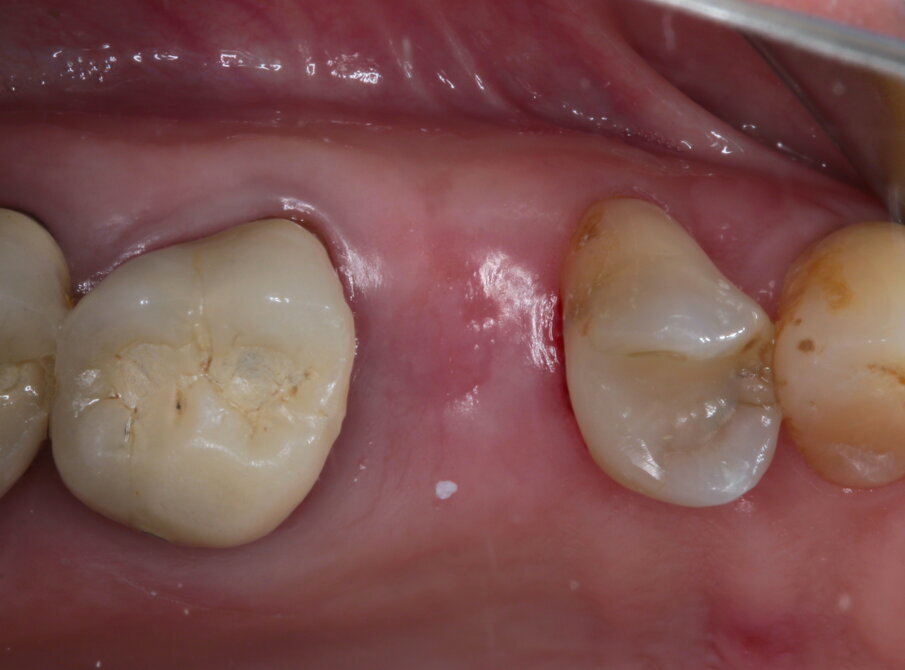

La paziente si presenta in visita lamentando mobilità e l’insorgenza di un dolore alla masticazione a carico dell’elemento 25. Clinicamente l’elemento presenta una corona in ceramica integrale realizzata anni prima (non ricorda quanti) presso altra sede, mobilità di II grado e sondaggio di 9 mm sul versante palatale.

Si presenta inoltre dolente alla percussione. Si riscontra anche l’assenza di risposta al test di vitalità dell’elemento 24, sul quale la paziente riferisce sia stata effettuata una medicazione endodontica da un collega come tentativo di risolvere la sintomatologia dolorosa a carico dell’elemento 25 (Figg. 1-3).